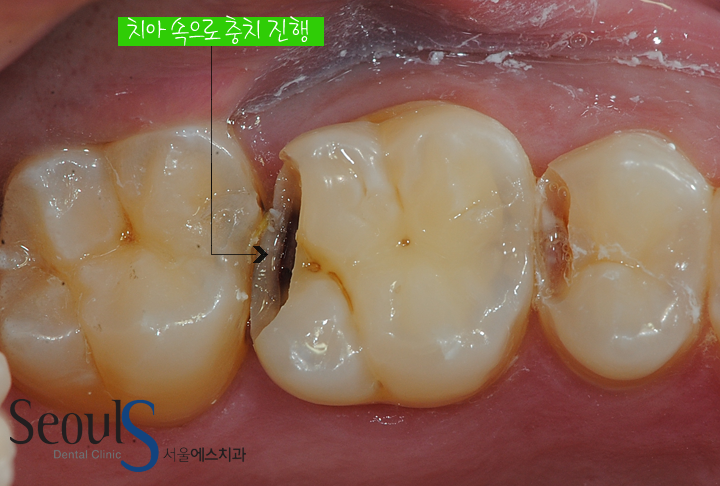

치아 속으로 진행되는 어금니 사이 충치에 대해 알아보겠습니다

사이 충치는 치아 사이에 음식물이 껴서 치아 속으로 충치가 진행됩니다

치아 속으로 진행되는 충치는 발견하기 어렵고

음식물이 낀 곳을 중심으로 양쪽 치아에 충치가 진행되는 경우가 많습니다

원으로 표시한 부분을 보시면 치아가 검게 보입니다

치아 속으로 진행되고 있는 충치 때문에 치아 표면이 검게 보입니다